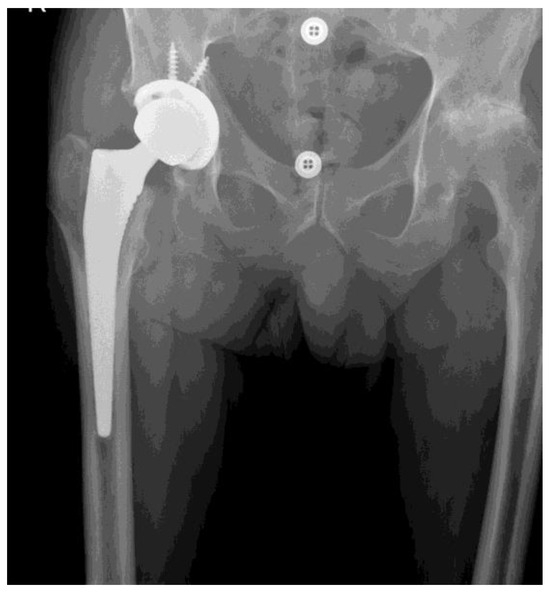

2. Methods

2.1. Study Group Characteristics

- Bertin, K.C.; Röttinger, H. Anterolateral mini-incision hip replacement surgery: A modified Watson-Jones approach. Clin. Orthop. Relat. Res. 2004, 429, 248–255. [Google Scholar] [CrossRef]